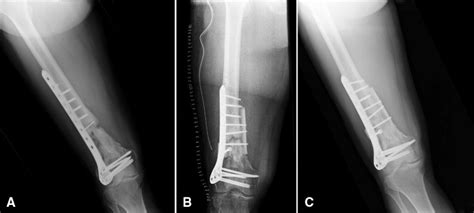

A femoral neck fracture is associated with high morbidity and mortality. Nonunion is permanent failure of healing following a broken bone unless intervention (such as surgery) is performed. High rate of fracture union if appropriate treatment is selected based on patient age and fracture pattern.

Prolonged immobility following the fracture may increase the risk of the following. In spite of advances in treatment, femoral neck fractures are complicated fractures with a relatively high incidence of nonunion. A fractured neck of the femur is always an emergency and reduction and fixation must be done in 24. Indications for conservative treatment of fractures of the shaft of the. Neck of femur fracture carries significant mortality with a tenth of patients dying in the first month and a third within the first year following the injury.3. What is a fracture nonunion? Valgus osteotomy of the femur is a suitable procedure for treatment of femoral neck nonunion in young patients, since it is easy to perform and yields relatively good results. These complications of fractures and their treatment are inevitable in some patients, but it is the concepts of slow union delayed union, and nonunion are based primarily on the state of activity and rate of progression of the repair process. For this prolonged period resulted in severe shortening and osteoporosis. Femoral neck fracture is a type of hip fracture common in elderly, osteoporotic women. What everyone with a non union fracture needs to know. Because they are easily applied, external fixators are often put on when a patient. Nail dynamization for delayed union and nonunion in femur and tibia fractures. Since this initial description by heng et al. Proximal femoral fractures are a very common disease which affect elderly patients after low energy trauma, but can also affect the young population as a consequence of high energy keywords: For example, if you are your healthcare provider might recommend nonsurgical treatment for a very young child, or for. Most femur fractures are fixed within 24 to 48 hours.